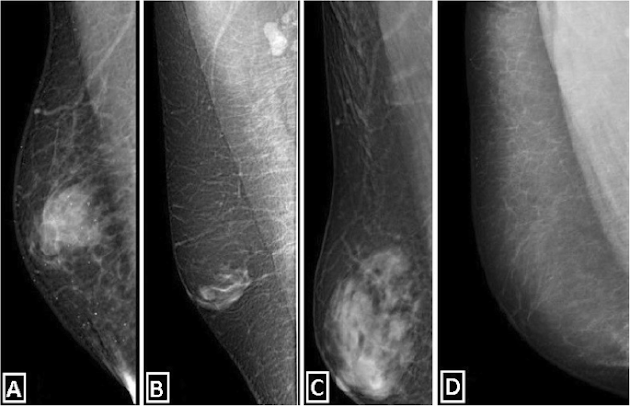

3. Ductal carcinoma in situ

Ductal carcinoma in situ (DCIS; also known as intraductal carcinoma) is considered non-invasive or pre-invasive breast cancer. In DCIS (also known as intraductal carcinoma), cells that lined the ducts have changed to look like cancer cells. The difference between DCIS and invasive cancer is that the cells have not spread (invaded) through the walls of the ducts into the surrounding tissue of the breast (or spread outside the breast). DCIS is considered a pre-cancer because some cases can go on to become invasive cancers. Right now, though, there is no good way to know for certain which cases will go on to become invasive cancers and which ones won’t. DCIS accounts for about 1 in 10 cases of breast cancer in men. It is almost always curable with surgery.

5. Infiltrating (or invasive) ductal carcinoma

This is the most common type of breast cancer. Invasive (or infiltrating) ductal carcinoma (IDC) starts in a milk duct of the breast, breaks through the wall of the duct, and grows into the fatty tissue of the breast. Once it breaks through the wall of the duct, it has the potential to spread to other parts of the body. Invasive (or infiltrating) ductal carcinoma (IDC) starts in a milk duct of the breast, breaks through the wall of the duct, and grows into the fatty tissue of the breast. At this point, it may be able to spread (metastasize) to other parts of the body through the lymphatic system and bloodstream. At least 8 out of 10 male breast cancers are IDCs (alone or mixed with other types of invasive or in situ breast cancer). Because the male breast is much smaller than the female breast, all male breast cancers start relatively close to the nipple, so they are more likely to spread to the nipple. This is different from Paget disease as described below.